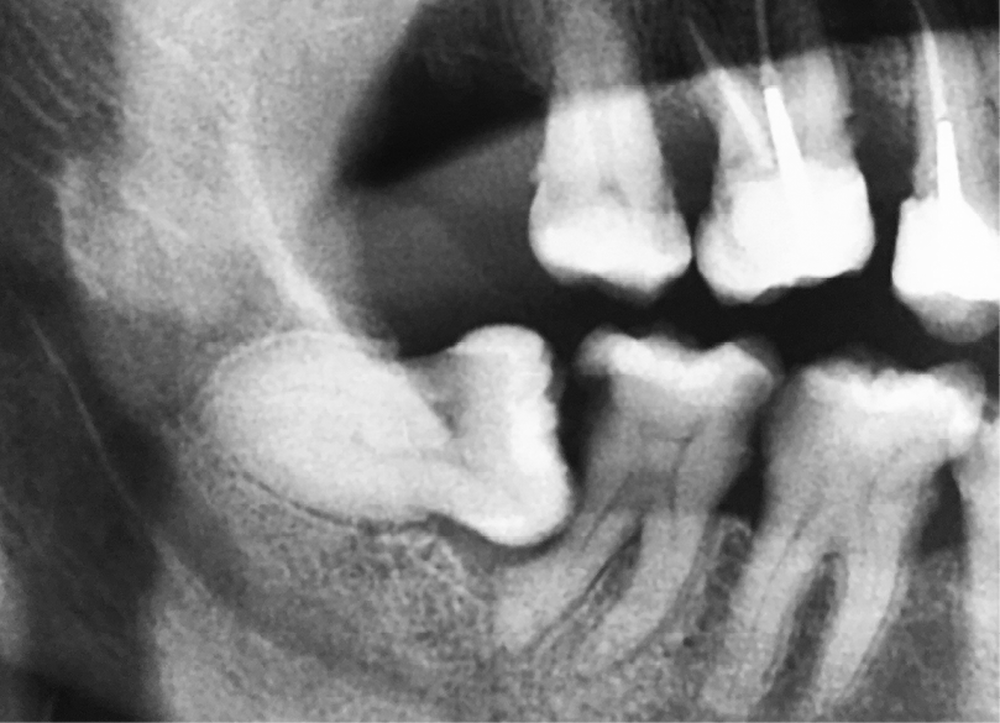

4a. Lésion parodontale en distal de 37 en rapport avec 38 mésioversée et une difficulté à l’hygiène.